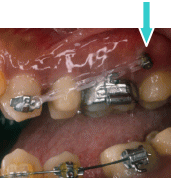

また、ケースによっては、K 1 といったミニインプラントも使用しています。このミニインプラントの表面は陽極酸化処理されているため、骨との結合がOSAS

よりも強固です。15歳以下の骨がまだ成熟していないケースに使用します。